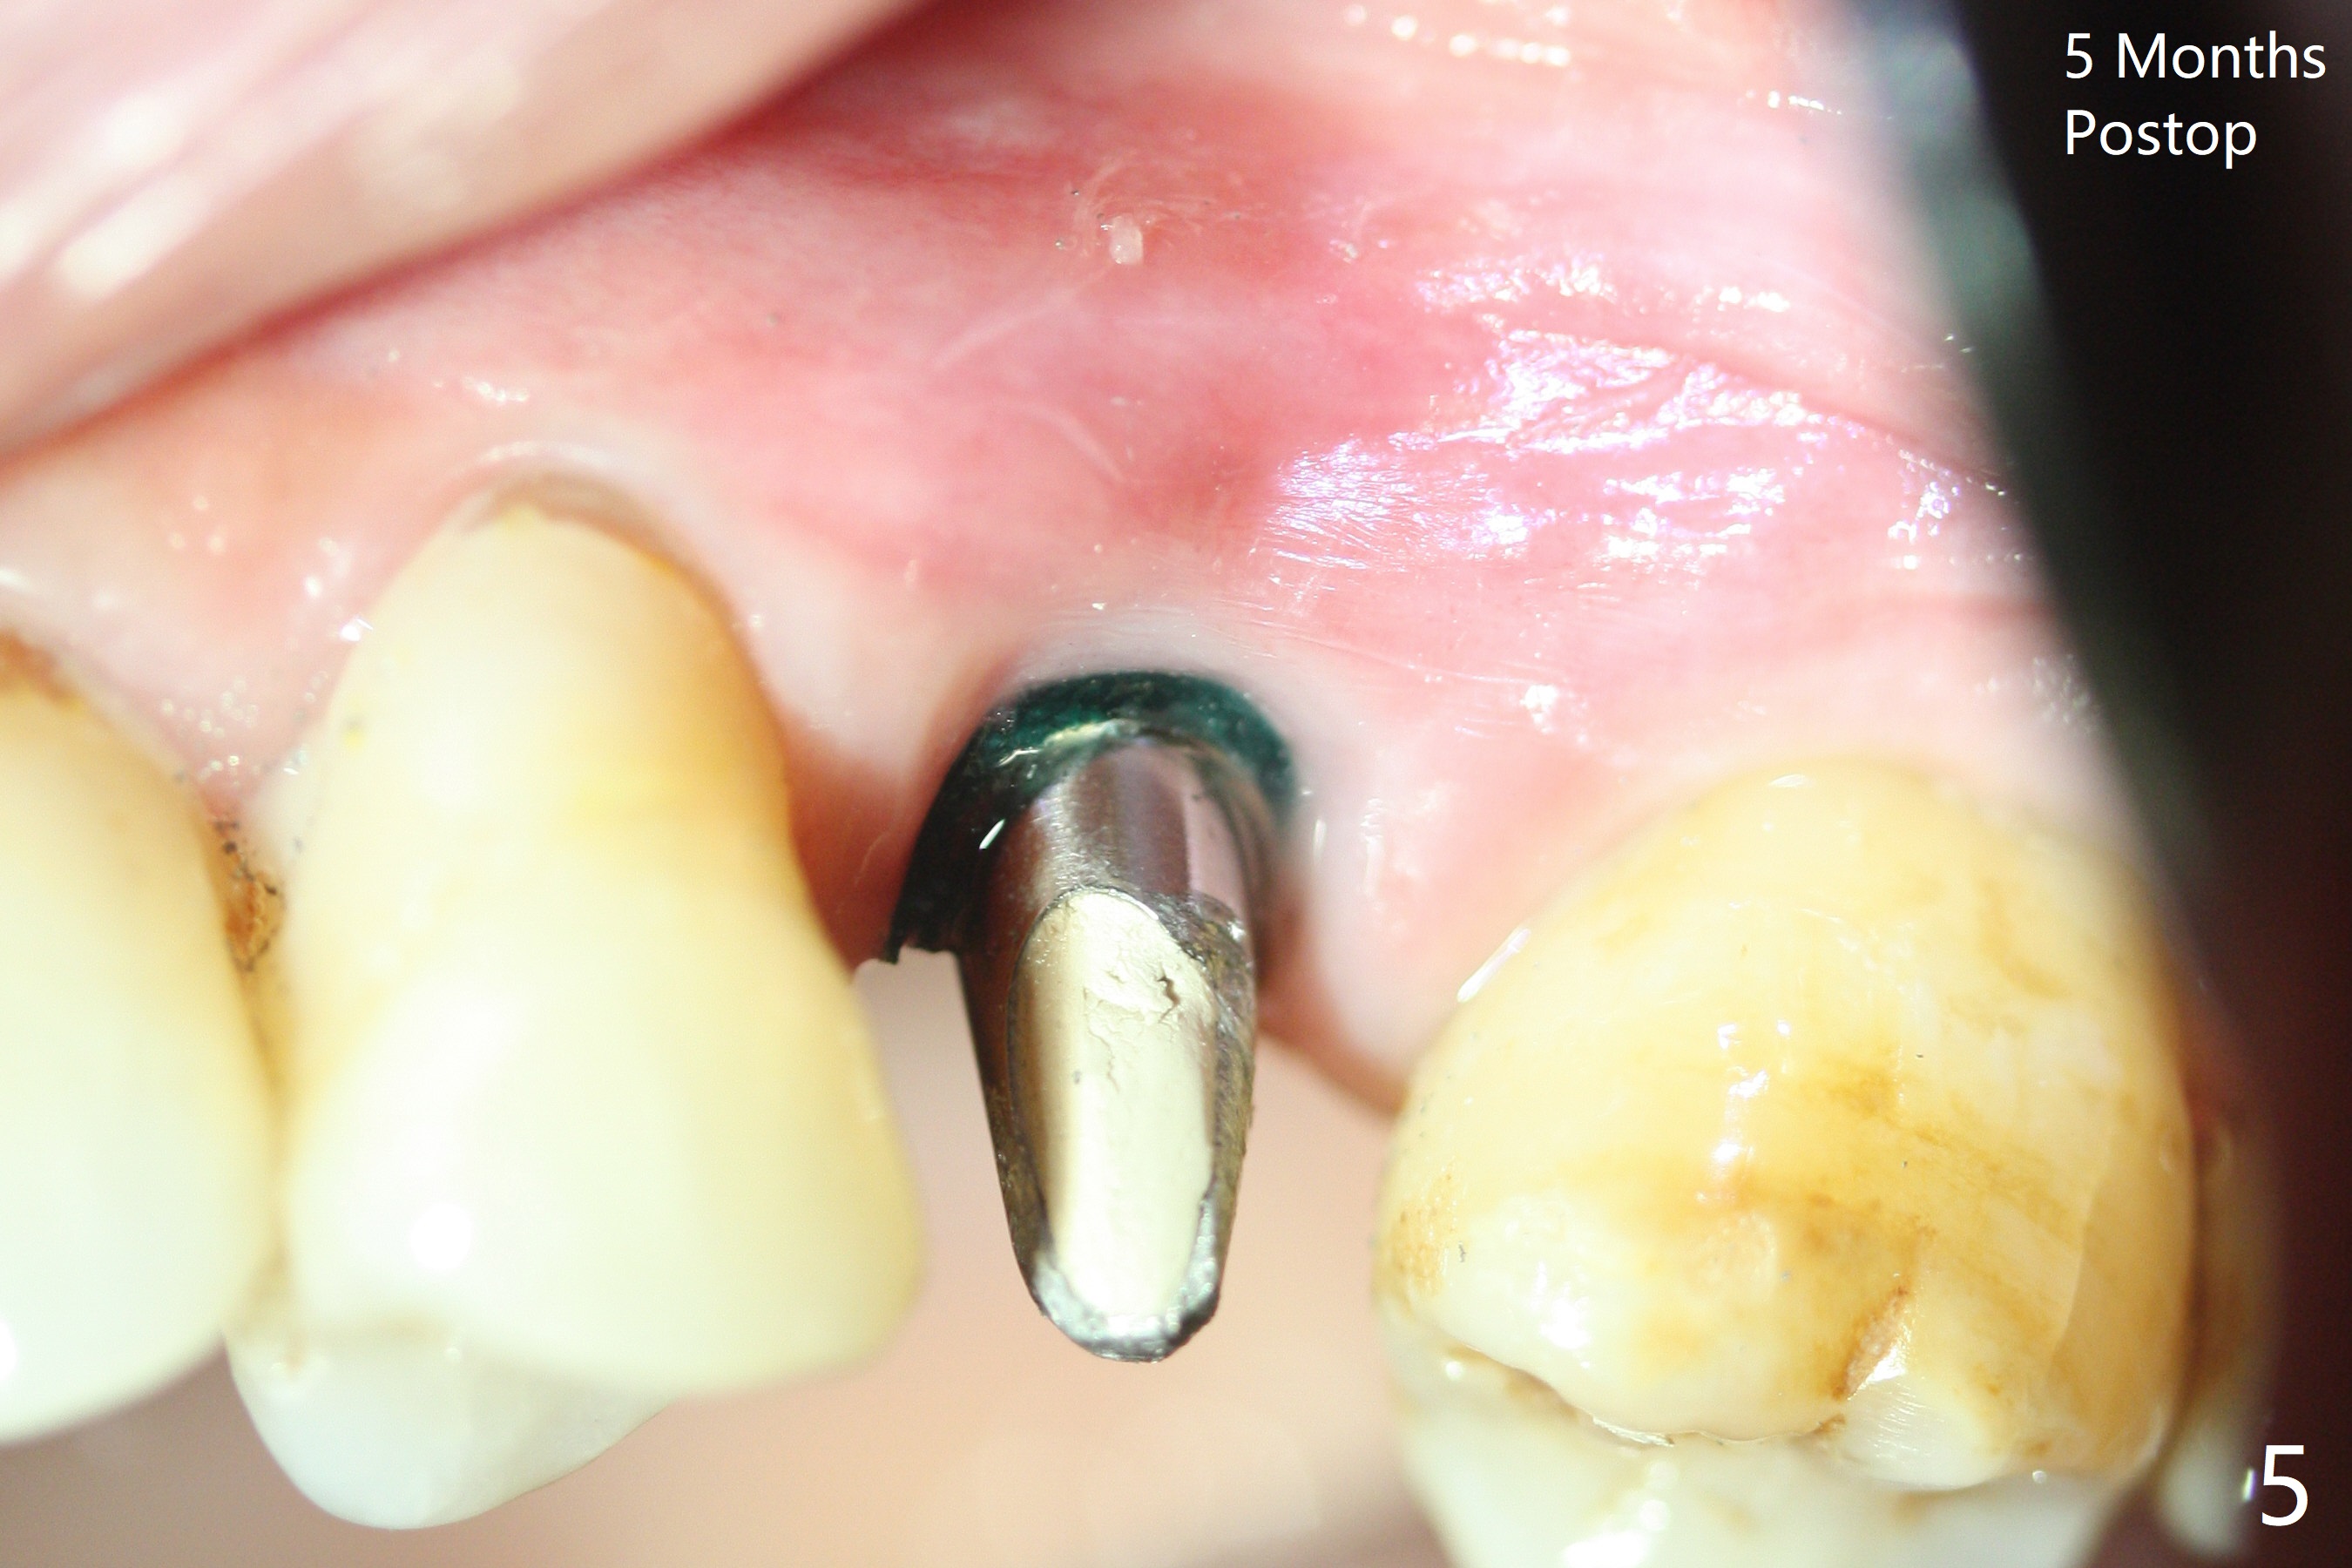

When a 2x16 mm parallel pin is inserted at #13 after extraction, PA does not show the upper end, as related to the long bone (Fig.1). In spite of underprep osteotomy, a 3.8x18 mm implant achieves ~ 20 Ncm of insertion torque (Fig.2). The long implant is still in the lower half of the triangular (cone-shaped) bone (Fig.3 red dashed line) between the nasal cavity (N) and the maxillary sinus (S). The bone is also wide. When a 4.5x5(5) mm abutment is placed, it is buccal. It appears that an angled abutment is needed for final restoration (probably 4.5x15 or 25 degrees, 5 mm cuff). When an angled abutment is placed 1 month posotp, the implant is found unstable. A healing abutment is placed (5.5x7 mm). Progressive loading is initiated 4-5 months postop. The implant becomes stable nearly 5 months postop (Fig.4), but the buccal gingiva is erythematous and tender, probably due to infected bone graft (one large piece), which is removed. One week later, the gingiva looks normal; impression is taken (Fig.5).